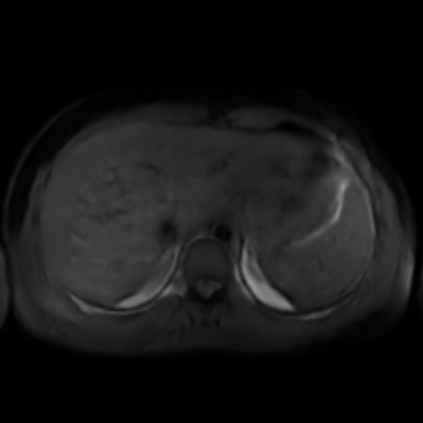

Motion artifacts are a primary source of magnetic resonance (MR) image quality deterioration with strong repercussions on diagnostic performance. Currently, MR motion correction is carried out either prospectively, with the help of motion tracking systems, or retrospectively by mainly utilizing computationally expensive iterative algorithms. In this paper, we utilize a novel adversarial framework, titled MedGAN, for the joint retrospective correction of rigid and non-rigid motion artifacts in different body regions and without the need for a reference image. MedGAN utilizes a unique combination of non-adversarial losses and a novel generator architecture to capture the textures and fine-detailed structures of the desired artifacts-free MR images. Quantitative and qualitative comparisons with other adversarial techniques have illustrated the proposed model's superior performance.

翻译:移动文物是磁共振(MR)图像质量恶化的一个主要来源,对诊断性能产生强烈影响。目前,MR运动的校正要么是预期性的,借助运动跟踪系统,要么是追溯性的,主要是利用成本昂贵的计算迭代算法。在本文中,我们使用名为MedGAN的新颖的对抗性框架,联合追溯性地校正不同身体区域的硬性和非硬性运动文物,而不需要参考图像。 MedGAN利用非对抗性损失和新型生成器结构的独特组合来捕捉无MR图象的纹理和精细详细结构。 与其他对抗性技术的定量和定性比较展示了拟议模型的优异性表现。